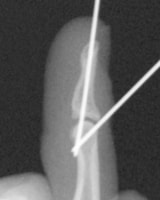

高精細デジタルX線イメージ

整形外科領域の手術において、骨を扱う際に必要なのがX線イメージです。当院では米ホロジック社製のフルオロスキャンを用いることにより、一般整形外科で用いる巨大なCアームでは見ることが困難な指骨の関節内骨折においても良好な整復操作を行うことを可能としています。